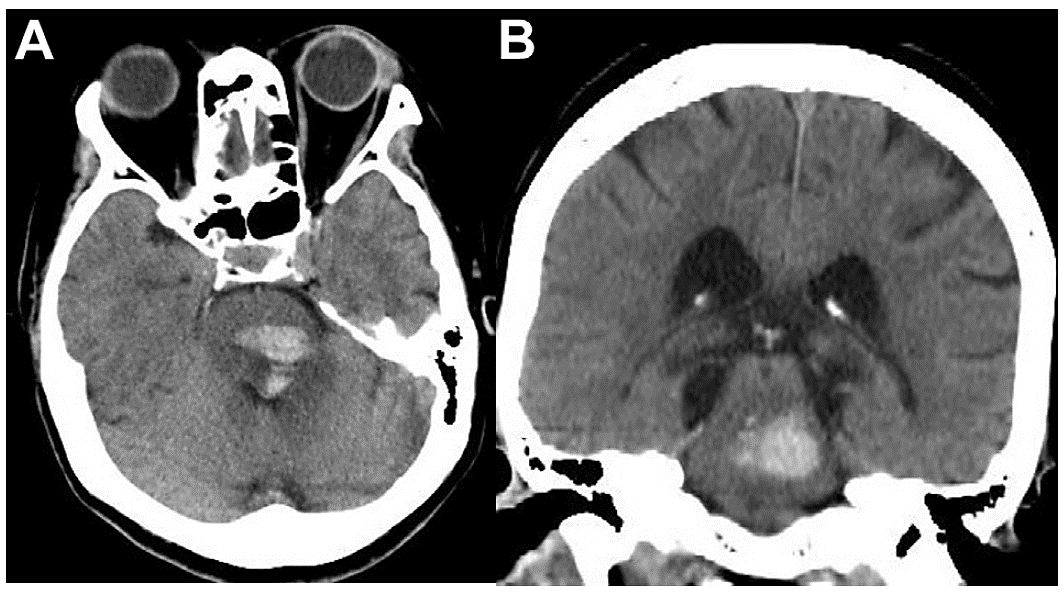

(图:ct扫描可见双侧脑桥出血,右侧明显)

术后1d复查ct,见脑桥双侧,中脑中部及右侧,左侧小脑,右侧颞叶内侧